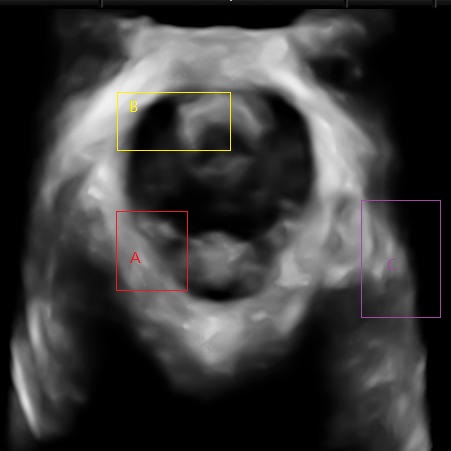

There are several challenges for the segmentation of levator hiatus from ultrasound images. We show some of them in Fig.1. First, some of the levator hiatus boundaries are blurry, weak or even missing (Fig.1 A). Second, the intensity is extremely inhomogeneous inside the levator hiatus. For example, the urethra may have similar intensity performance with the muscles around the levator hiatus(Fig.1 B). Third, pixels in the background region may have similar intensity performance with the region inside the levator hiatus (Fig.1 C). In order to overcome these difficulties while segmentation, we proposed a multi-scale framework based on local image information and boundary shape similarity.

Refer to caption

Figure 1: Challenges for the segmentation of levator hiatus.